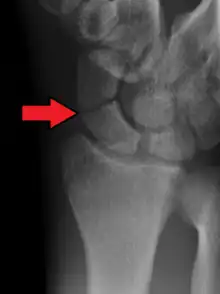

Le diagnostic de fracture est difficile à réaliser car les lésions éventuelles peuvent ne pas être immédiatement visibles sur les radiographies standard du poignet de face et de profil. On pratique aussi une radiographie avec incidences spéciales (inclinaison de 30° vers le coude) qui permettent de dérouler l'os et ainsi de visualiser plus précisément le trait de fracture[5].